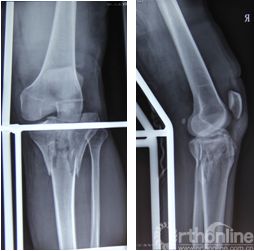

胫骨平台是位于胫骨上端的一个平台,与股骨的髁部形成膝关节。胫骨平台骨折是指胫骨平台部位发生的骨折,可能是由于直接撞击、跌倒或扭伤等原因引起。根据骨折的严重程度和位置,可分为多种类型,如单纯骨折、粉碎性骨折等。

无移位的胫骨平台骨折

胫骨平台关节面塌陷小于2mm